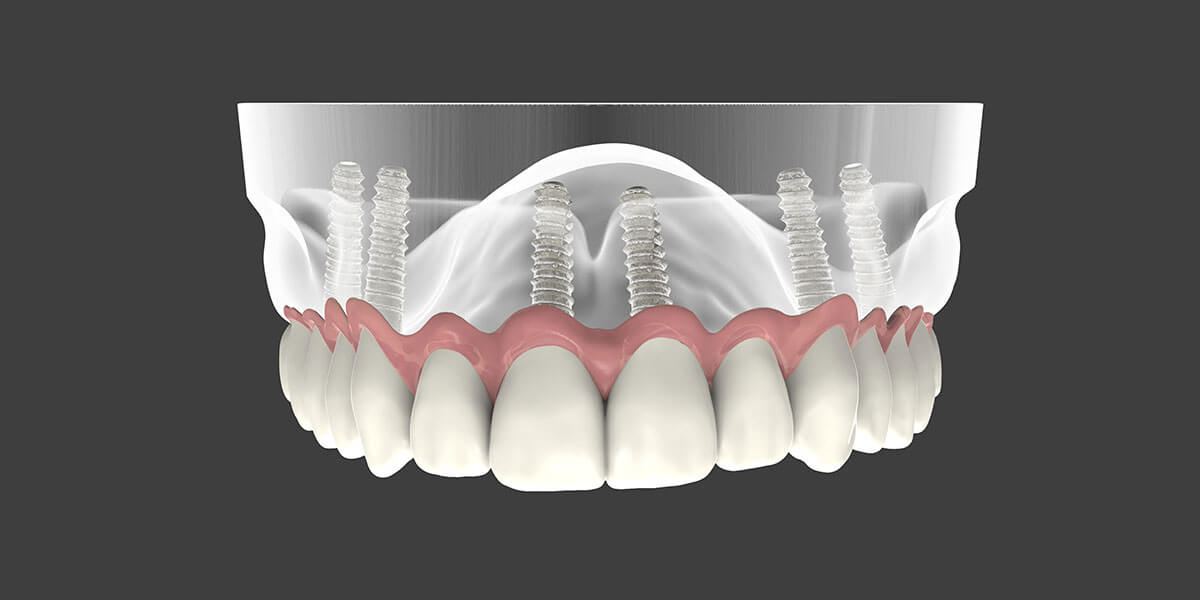

Dental implant supported dentures can be either fixed or removable.

This solution requires the placement of two or more implants. If a removable denture is selected, the denture will “snap” on to the implant rather than requiring the use of denture paste or adhesives. Removable dentures can be taken out for cleaning at night.

Easy to care for, this solution can simulate the look and feel of natural teeth and stay fixed in place with the implants acting as anchors. Patients will not experience the typical rocking and movement or gum irritation associated with dentures.